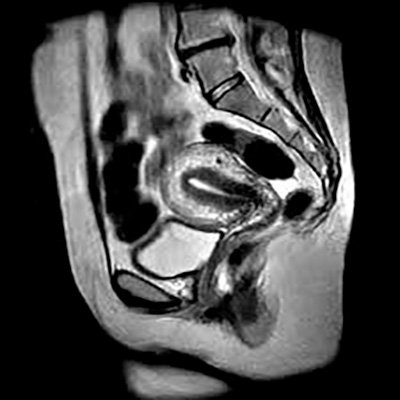

Gracias a las avanzadas técnicas, podemos estudiar los órganos abdominales (hígado, páncreas, etc) así como pélvicos (útero, ovario, próstata) con una gran diferenciación hística, que con el apoyo de medios de realce tisular (contraste) nos permiten un afinamiento en el diagnóstico. Es posible que estos estudios necesiten de la inyección de contraste, con lo que es recomendable que el paciente venga en ayunas. Puede que en algún momento de la prueba se le pida que realice apneas, todas ellas controladas y adaptadas a la capacidad del paciente

Ejemplos